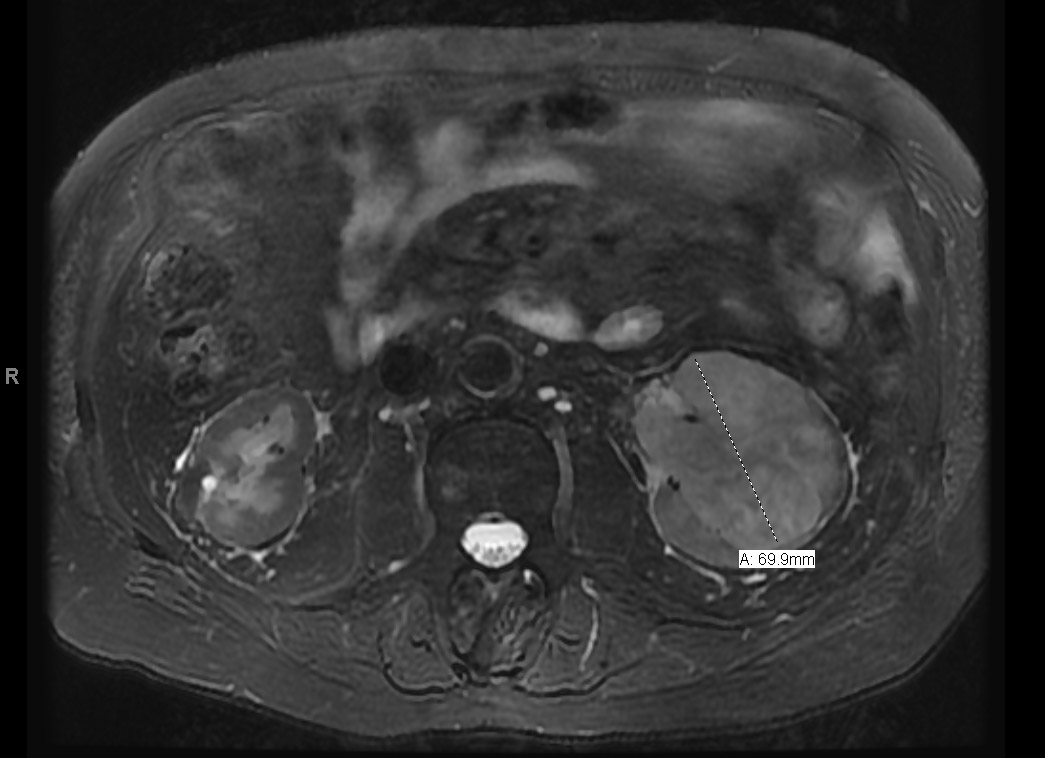

CT scan revealed a left renal mass. MR imaging of the abdomen revealed a 7 cm infiltrating left-sided renal mass which extended into the collecting system and proximal ureter (Fig. 1). Also seen was a 3.7 cm. enhancing, heterogeneous soft tissue mass involving the renal pelvis and proximal ureter.